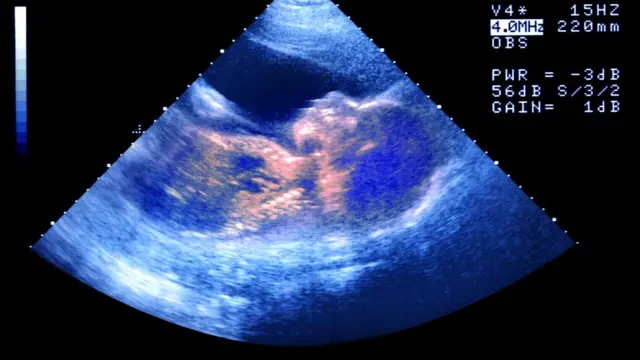

La madre de cinco hijos dijo que quería hacerse un aborto y que en el centro le dijero por teléfono que podría hacerse uno allí. Cuando llegó a su cita, dice que le aseguraron que necesitaba hacerse un ecografía. Esta mostró que estaba embarazada de mellizos.

"Me dijeron 'tienes que mirar, estos son tus bebés' y cuando finalmente giré para mirar, y vi a dos pequeños bebés en la pantalla, me limpié mi propio gel y me fui de la habitación... Eso fue demasiado para mí".

Fuente de la imagen, Getty Images

Ashleigh se hizo finalmente un aborto y dijo que su experiencia en el Centro de Salud Stanton la había dejado traumatizada.

Lord criticó el uso de ecografías en los centros de orientación sobre el embarazo. Dijo: "Las ecografías son una herramienta y pueden usarse en algunas circunstancias, pero en otras pueden ser bastante intrusivas".

El uso de ecografías, añadió, puede provocar culpa en las mujeres embarazadas que están considerando abortar y por tanto pueden ser manipuladoras.